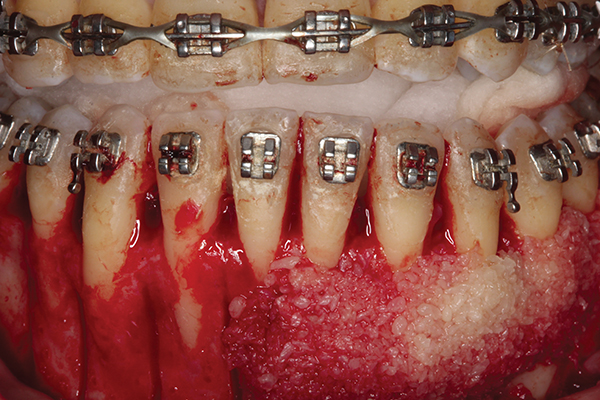

Fig 4. Particulate corticocancellous mineralized freeze-dried bone allograft in place on the left half of the mandible for periodontal regeneration and alveolar augmentation.

Figure 4

Fig 5. Bone grafting complete. Collagen wound dressing in place for graft stabilization and autogenous connective tissue grafts in

place, teeth Nos. 21 and 22 and Nos. 27 and 28, for simultaneous soft-tissue augmentation.

Figure 5